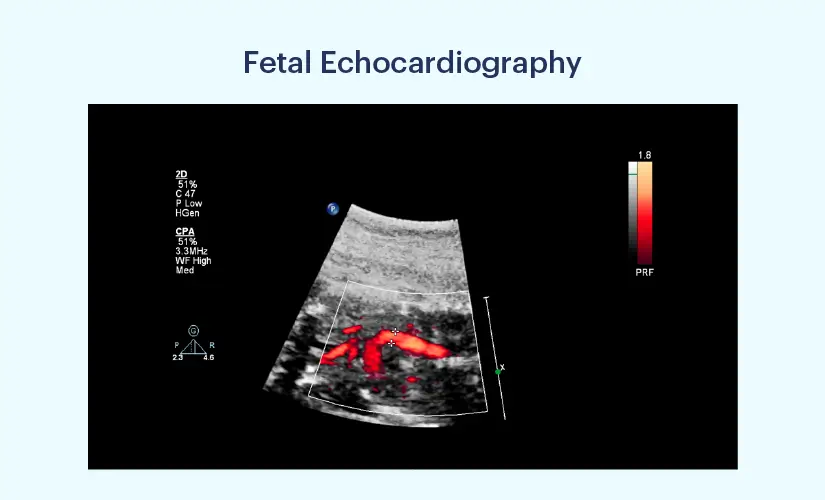

It is a procedure that uses sound waves to check the heart of a foetus. A foetal echo is useful in finding heart defects before the child's birth. If the defect is detected earlier, healthcare providers may treat the problem before birth, if possible. It also prepares the medical staff and parents for any complications during labour. In some cases, healthcare professionals can advise an early delivery. Foetal Echocardiography is often done in the second trimester if there is a family history of heart issues. There could be many reasons why your doctor could suggest this test. Some reasons can be the following:

A foetal echo isn’t usually a risky procedure for the mother or the foetus. For this echo, healthcare professionals use the lowest possible setting of Ultrasound. The procedure can usually take anywhere from 30 minutes to 2 hours. A trained paediatric cardiologist, obstetrician, radiologist, or maternal-foetal specialist can conduct the procedure.

The mother will be asked to lie on a table, and the medical staff will apply a gel to the stomach. Then, they will use a transducer, a device that sends out sound waves. Then, they will move around the device till they get a good image of the foetal heart. The mother may experience some pressure as the transducer moves around the stomach. After this, the foetal echo is complete. Afterwards, they will look at the results and then decide on a future treatment plan.